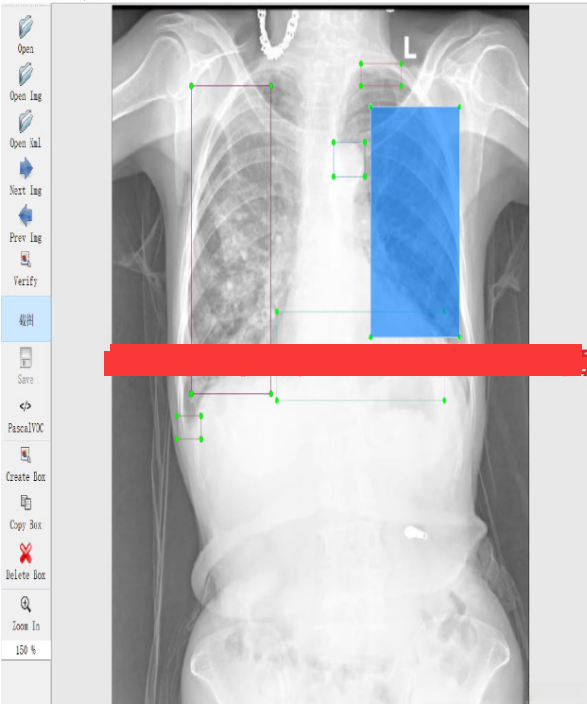

使用YOLOv8来训练——心胸肺CT检测数据集,并使用训练好的模型进行预测。

具体说明如何利用YOLOv8这一工具对包含约4100张心脏与胸部影像的心脏及胸部相关CT检测数据集进行系统性训练,并完整提供相应的训练代码及操作指南。

模型预测

你可以使用训练好的模型对新图像进行预测:

ultralytics predict model=best.pt source=path/to/your/image.jpg imgsz=640